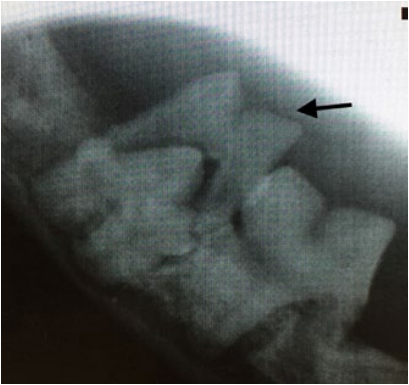

- Неправильная траектория прорезывания (фото 2). Такая патология может возникать из-за нарушения развития альвеолярного отростка в результате какого-либо механического препятствия, нарушения закладки зачатков зубов в раннем эмбриональном периоде, а также по причине дефицита места.